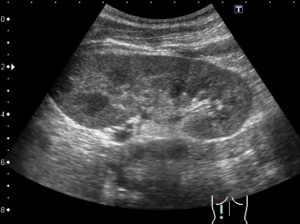

Хронический пиелонефрит

Ультразвуковое исследование при хронической патологии показывает уменьшение органа в размерах и сморщивание его коркового вещества. При многолетнем вялом течении болезни можно обнаружить в паренхиме рубцовую ткань или очаг склероза. Такие неспецифические признаки могут иметь место и при других патологиях.

Таким образом, при хроническом пиелонефрите на УЗИ могут наблюдаться:

- Неровные контуры органа,

- Асимметрия размеров,

- Деформированная, возможно расширенная чашечно-лоханочная часть органа,

- Диффузная неоднородность паренхимы,

- Повышенная эхогенность.

Параметры хронического пиелонефрита:

- повышенная эхогенность;

- уменьшение размеров паренхимы;

- превосходство по площади почечного синуса;

- наблюдается повышенная эхоплотность паренхимы;

- контур органа имеет выраженную бугристость;

- почка имеет тенденцию к уменьшению;

- увеличение чашечно-лоханочной системы.

УЗИ-признаки хронического пиелонефрита

Чтобы обнаружить очаг воспаления почек, определить нарушения почек и мочевыводящих путей назначают ультразвуковое исследование. При этом признаками заболевания, характеризующегося хроническим течением, считаются:

- уменьшенные размеры почек;

- бугристость очертаний органа;

- деформация или расширение чашечно-лоханочной системы;

- истончение основной ткани почек, ее повышенная эхогенность.

Эхограмма при хроническом пиелонефрите

Размеры почек, как правило, не изменены. Если развился нефросклероз, орган уменьшается в объеме.

Если патологический процесс односторонний, наблюдается асимметрия в размерах правой и левой почек.

Неровность наружного контура – свидетельство инфильтрации паренхимы.

Зона нормальной почечной ткани уменьшена, паренхима содержит мелкие и крупные рубцы и участки кальцификатов, от которых отходят эхосигналы различной величины.

Лоханка расширена, тонус повышен, стенки чашечки утолщены.

Деформация чашечно-лоханочной архитектоники свидетельствует о вторичности пиелонефрита, который сформировался на фоне гидронефроза или врожденной аномалии.

Иногда в зоне паренхимы или на поверхности обнаруживаются вторичные кисты – мелкие жидкостные образования до 2 см в диаметре. На эхограмме выглядят как анэхогенные участки.